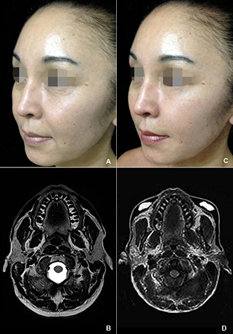

Twenty females underwent FR-HA in a single session for up to eleven facial zones, average of 6.95±1.30 facial zones per patient and average of 30.55±0.74 injection points per facial zone. Each patient received an average of 16.80±0.83 injections points per treatment. Table 1 detailed number of injection points and volume of HA-injected in eleven facial zones for each patient. The volume of HA injected was 49.50 ml, average of 4.50±0.37 ml per facial zone and 2.48±0.12 ml per patient. The volume of SubQ-product was 29.15 ml to forehead, cheek, nasolabial fold, marionette lines and jawline; of Deep-product was 11.00 ml to crow's feet, lip philtral ridge, chin and jowls; and of Fine-product was 9.35 ml to glabella, tear trough, and lip vermillion, cupid's bow and white roll. Table 2 exhibited for each facial zone the number of patients and injection points, and distribution of injection technique and volume of the HA-products. FR-HA through volumetric expansion, projection and lifting provided by SubQ, Deep and Fine products in eleven facial zones recovered the forehead, glabella and crow's feet wrinkles; lid-cheek junction, cheek, nasolabial fold, marionette line, chin and mandible contour; and lip fulness, contour and philtral ridge, reaching a youthful appearance for the aging-face (Figure 3).

Figure 3 (A) At baseline, 51-year-old female with aging-changes of whole face.

(B) Twenty-four hours after injection of 3.60 ml of HA-products in eleven facial zones, being 2.15 ml for SubQ-product, 0.75 ml for Deep-product and 0.70 ml for Fine-product.

(C) At one-month, recovery of the more youthful face appearance.

(D) No significant changes from one-month to twelve-months, with an even younger appearance than that at baseline.

Volumetric augmentation of the cheek induced a lifting of lid-cheek junction, nasolabial fold and marionette line, well-evidenced through clinical outcomes and noticeable projection and symmetry of midface displayed in MRI on axial plane at one-month (Figure 4). Efficacy and long-lasting of FR-HA by using the SubQ, Deep and Fine products in specific facial zones were evidenced by noticeable recovery of the symmetry and balance of the youthful appearance from one-month to twelve-months, displayed in MRI on coronal plane with no significant changes in density, size and symmetry of the gel-diffusion, indicating that the HA-products injected remained stable in the facial zones with no significant resorption or loss of the correction in the same period (Figure 5). Minimal differences on clinical outcomes and no significant changes of the gel-diffusion in MRI on coronal plane were endorsed by FOE scores of 74.38% at one-month and 71.13% at twelve-months. Table 3 exhibited the FOE questionnaire scores of the patient's perception of its facial appearance before and after FR-HA. Side effects as erythema, bruising and swelling regressed within days. No major complications as asymmetry, granuloma, gel migration, infections, and harm of the facial nerve, skin necrosis or blindness occurred in this series of patients.

Figure 4 (A) 52-year-old female with midface deflation.

(B) At one-month, recovery of the midface youthful appearance with 2.20 ml of HA-products, being 1.60 ml for SubQ-product, 0.20 ml for Deep-product and 0.40 ml for Fine-product.

(C) MRI in T2-weighted with fat suppression on axial plane showing no zygomatic-malar projection.

(D) At one-month, symmetrical midface projection by a gel-diffusion pillar in the cheek displayed through transverse section of the gel-diffusion.

Figure 5 (A) 52-year-old female with a flaccid and hanging face. Patient requested a HA-rhinoplasty twenty-days after FR-HA, not considered in the study protocol.

(B) At one-month, recovery of the youthful appearance with 3,55 ml of HA-products, being 2.50 ml for SubQ-product, 0.20 ml for Deep-product and 0.85 ml for Fine-product.

(C) At twelve-months, no significant changes on the face appearance.

(D) MRI on coronal plane at baseline.

(E) At one-month, distribution of the gel-diffusion on the facial zones.

(F) No significant HA-degradation at month-twelve, corroborating with no significant changes on the face appearance.